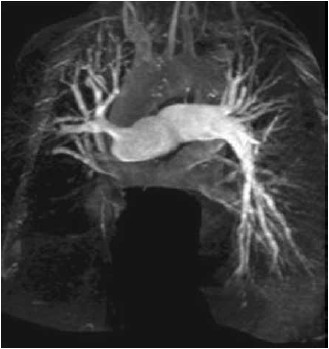

Mulher de 32 anos apresenta dispneia progressiva aos esforços no último ano. O exame físico é notável para: pressão arterial: 123 x 81 mmHg; frequência cardíaca: 91/min, saturação de oxigênio: 91%; pulmões limpos; ausculta cardíaca com componente pulmonar alto de B2; edema simétrico de membros inferiores. Há 4 meses ela usa furosemida, enalapril e apixabana, com pouca melhora clínica. O cateterismo cardíaco direito mostra: pressão atrial direita: 14 mmHg; pressão arterial pulmonar (média): 38 mmHg; resistência vascular pulmonar: 6,8 unidades Wood (544 dinas por segundo por cm-5); pressão capilar pulmonar: 8 mmHg. A angiografia pulmonar é mostrada a seguir.

(Arquivo pessoal: imagem usada com autorização.)